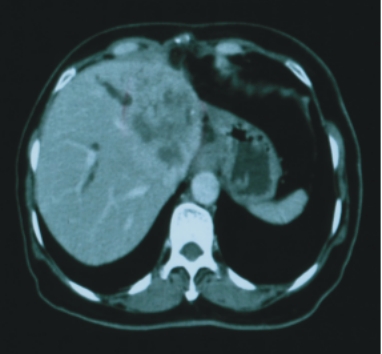

37歲/女性

(肝內膽道癌術後復發) |

| 90/10/12(治療前)

|

| 腫瘤大小:7x6x5公分 |

完全消失 |